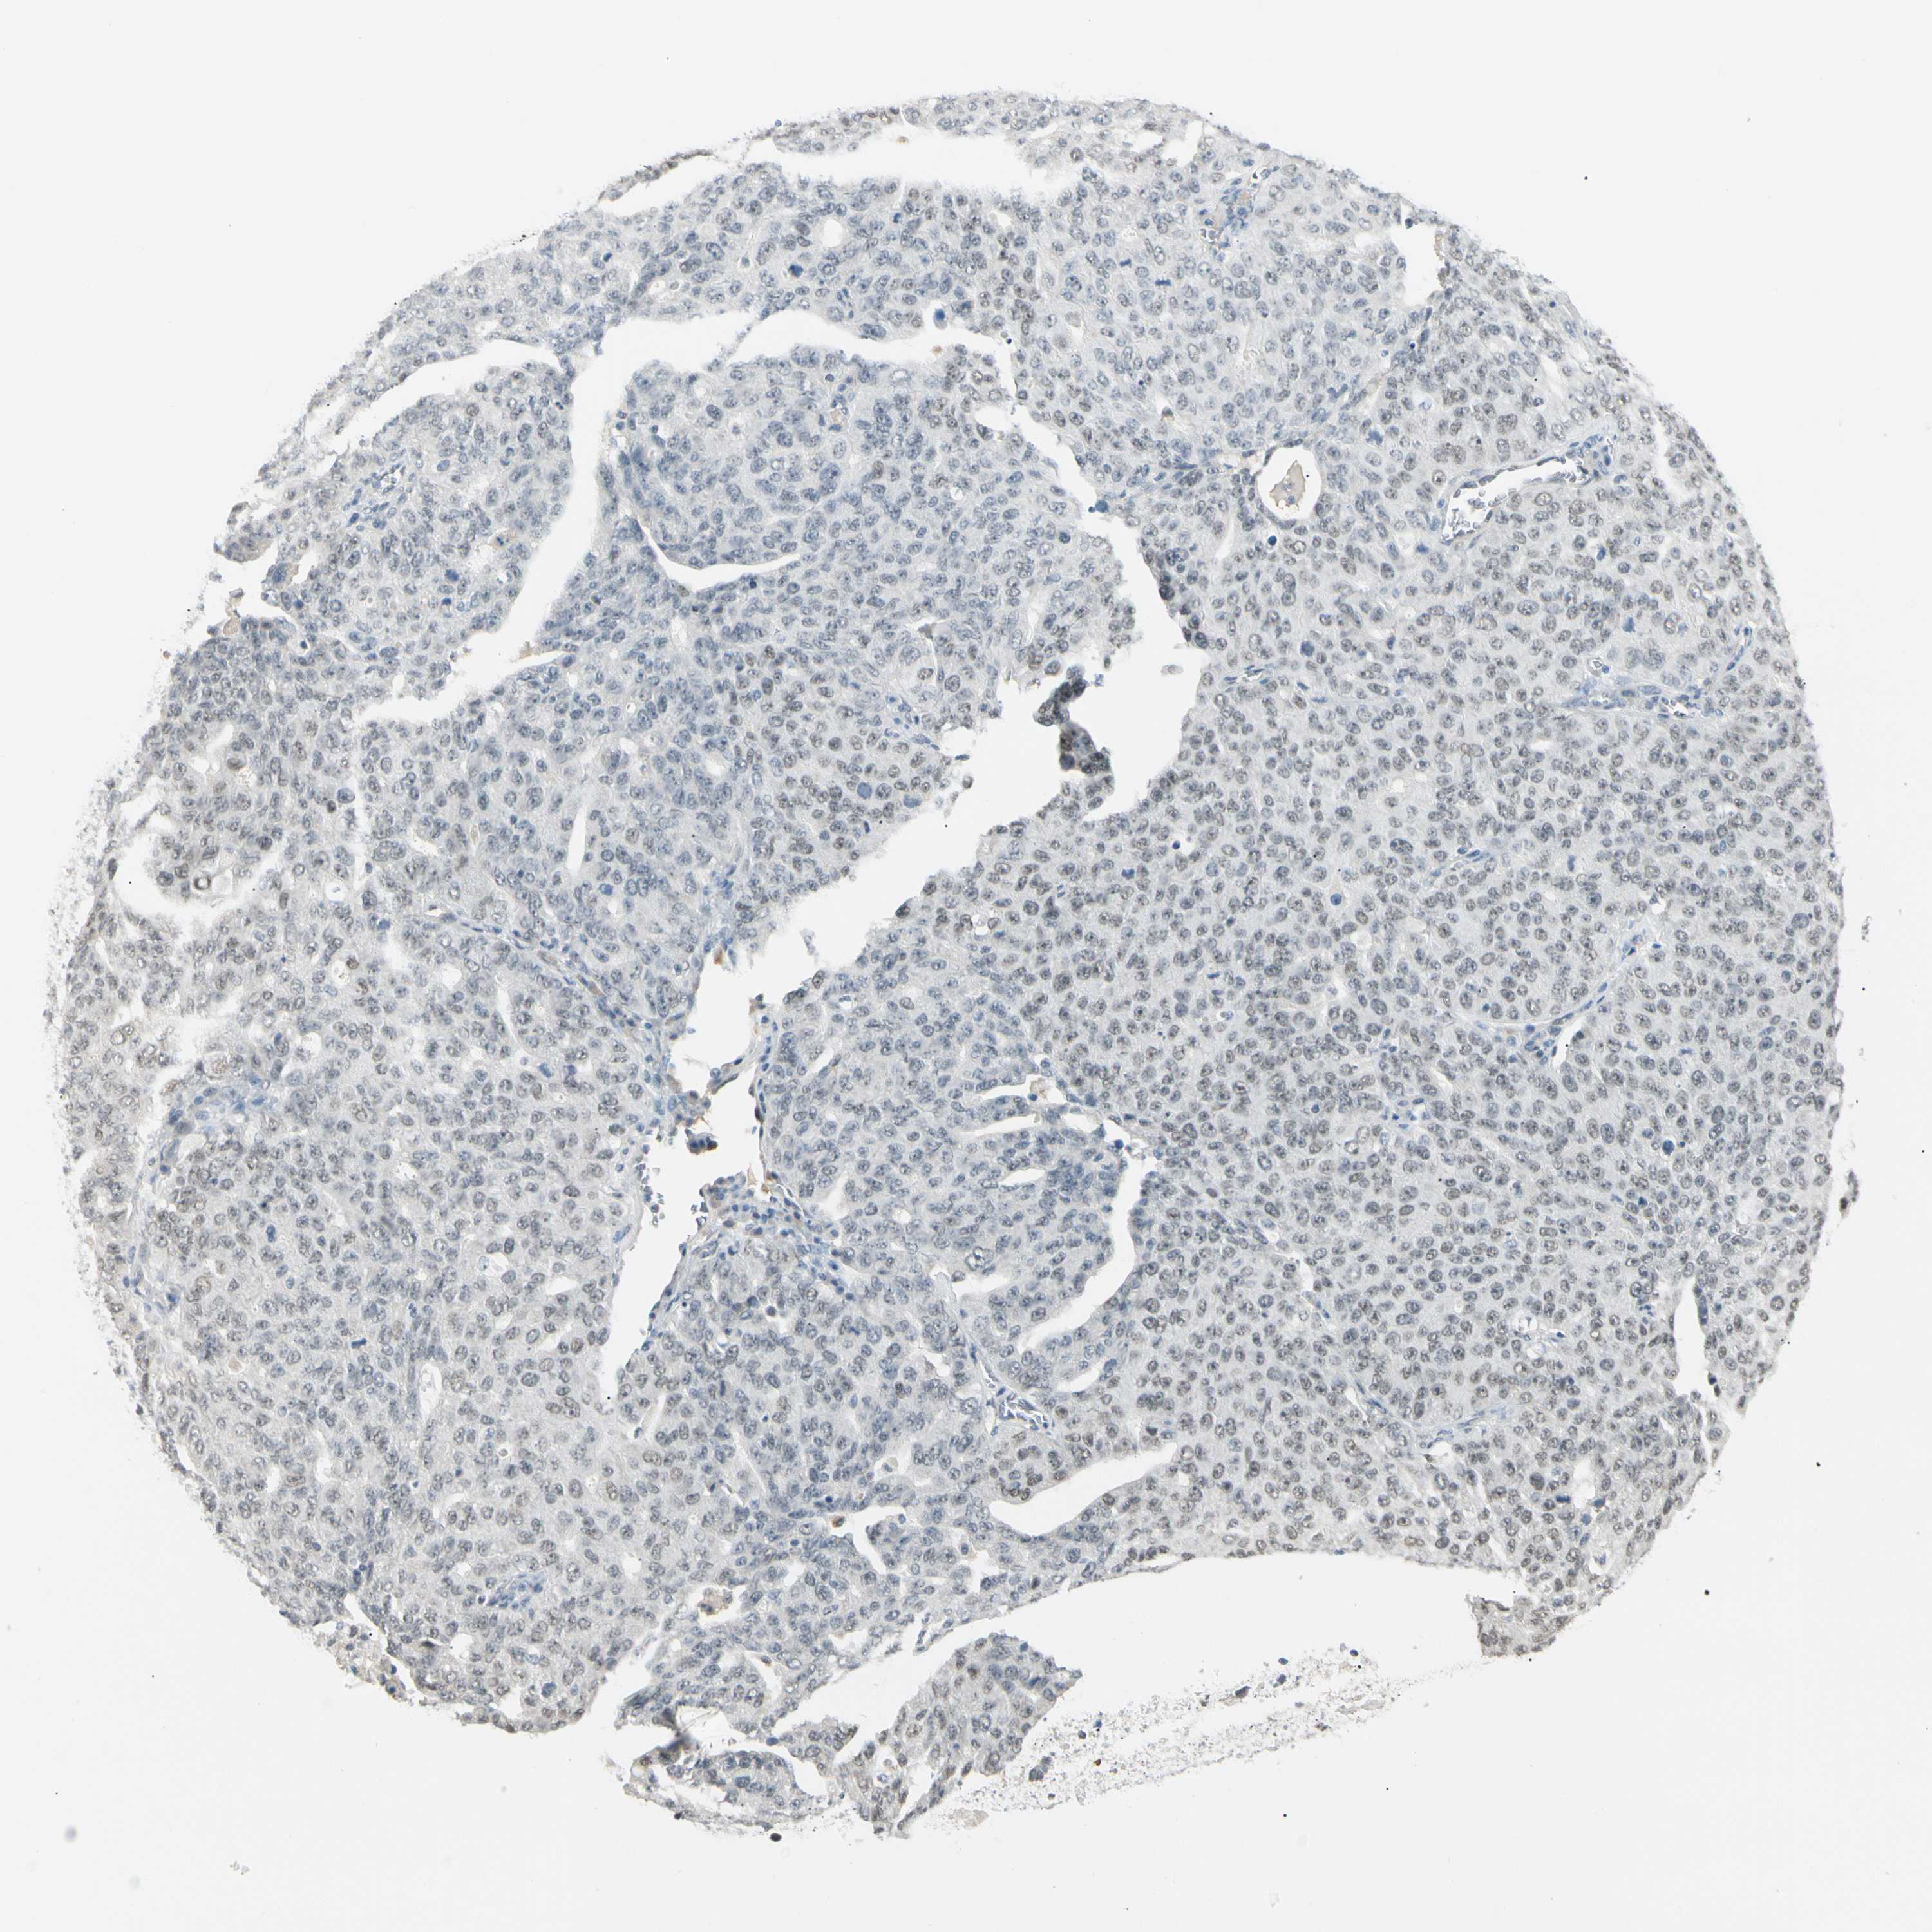

OVARIAN CANCER - Protein expressioni

A mouse-over function shows sample information and annotation data. Click on an image to view it in a full screen mode. Samples can be filtered based on level of antibody staining by selecting one or several of the following categories: high, medium, low and not detected. The assay and annotation is described here.

Note that samples used for immunohistochemistry by the Human Protein Atlas do not correspond to samples in the TCGA dataset.

Antibody stainingi

Antibody staining in the annotated cell types in the current human tissue is reported as not detected, low, medium, or high, based on conventional immunohistochemistry profiling in selected tissues. This score is based on the combination of the staining intensity and fraction of stained cells.

Each image is clickable and will lead to virtual microscopy that enables deeper exploration of all samples and also displays staining intensity scores, fraction scores and subcellular localization as well as patient and tissue information for each sample.

Antibody HPA008435

Cystadenocarcinoma, mucinous, NOS